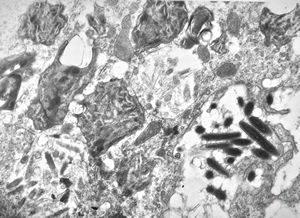

F,58y. | Whipple disease

Whipple disease